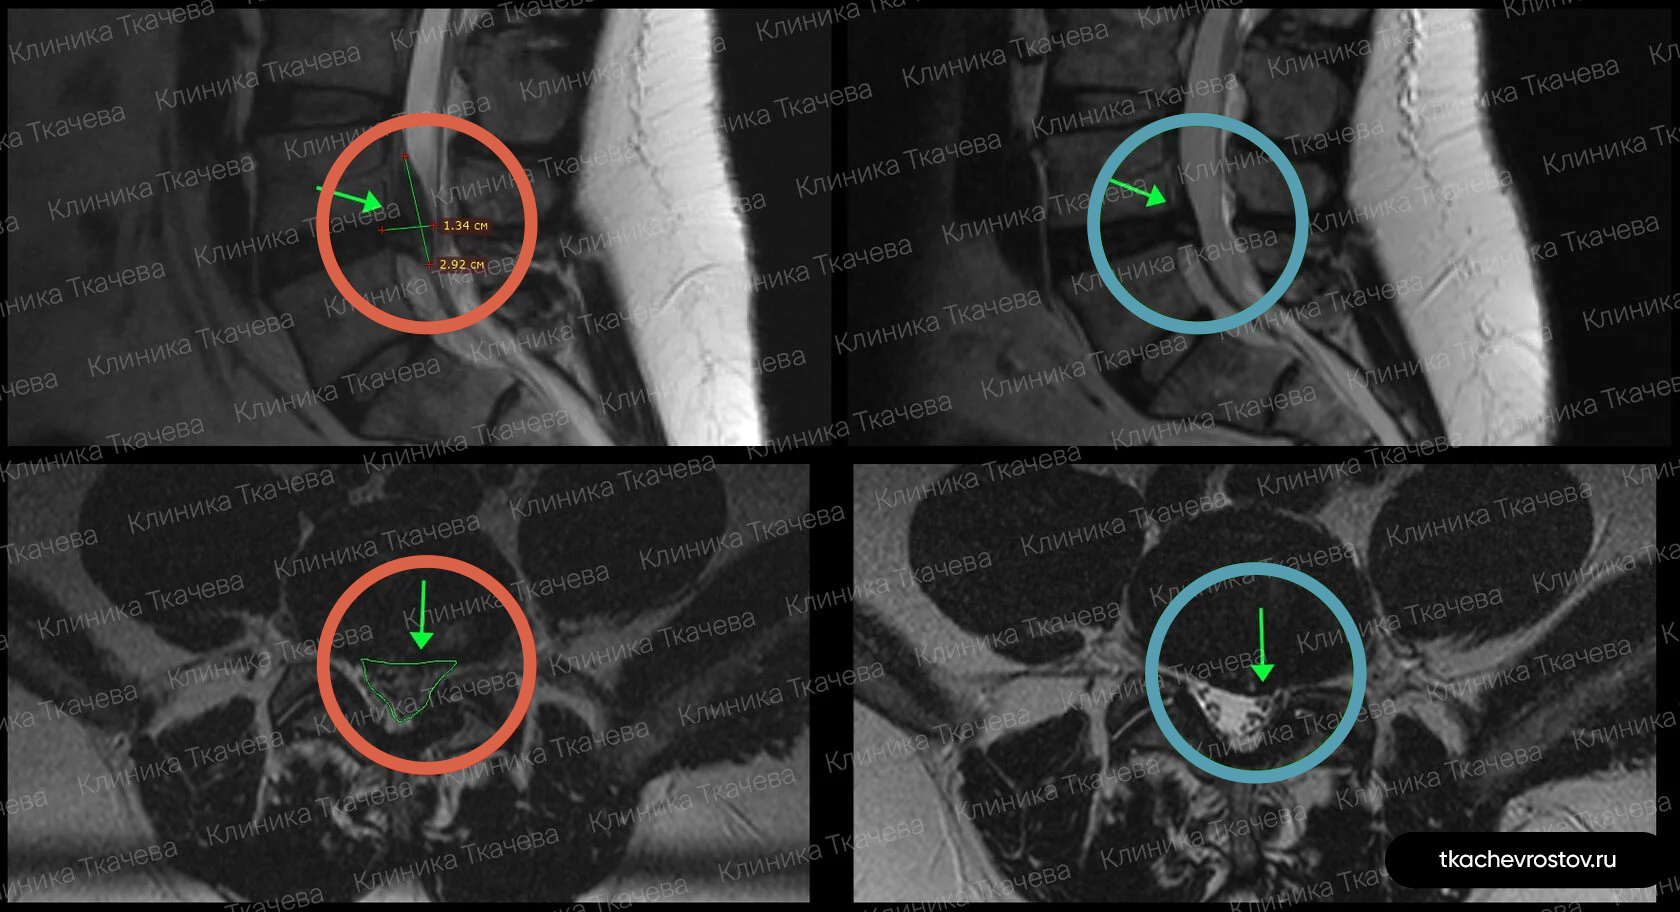

Грыжа в поясничном отделе L5-S1

Мужчина. Секвестрированная грыжа в поясничном отделе L5-S1 1.3 x 3.2 см. Невыносимая боль, хромота и критическое снижение нейропроводимости обеих ног. Никаких альтернатив кроме операции не предлагалось.

ДО:

-

Упражнения с физиотерапевтом и блокады

- Длительная отрицательная динамика

- Невыносимая боль

- Хромота и онемение пальцев ног

- Критическое снижение нейропроводимости обеих ног

- Потеря трудоспособности и ограничение жизнедеятельности

ПОСЛЕ 1 курса:

✓ Наступила полная резорбция грыжи

✓ Наступило улучшения общего состояния

✓ Регрессировали боль и онемение в ноге и пальцах

Пациент прошел 1 курс лечения (12 дней).